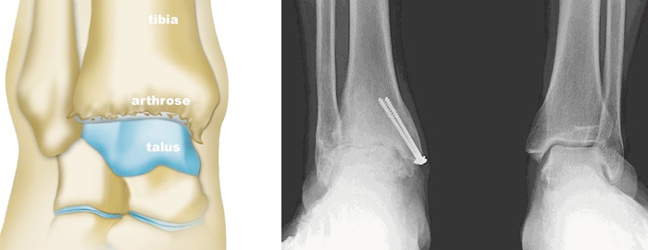

C’est l’usure du cartilage de l’articulation de la cheville, entre le tibia et le talus. Elle entraîne généralement des douleurs, des gonflements et une raideur de la cheville, ces symptômes s’aggravant avec le temps.

Enfin lorsque le traitement médical est inefficace, la chirurgie sera envisagée. Le traitement conservateur est favorisé, par opposition à la prothèse de cheville dont les indications restent rares. Il consiste le plus souvent à réaliser une « arthrodèse » c’est à dire un blocage de l’articulation de la cheville.